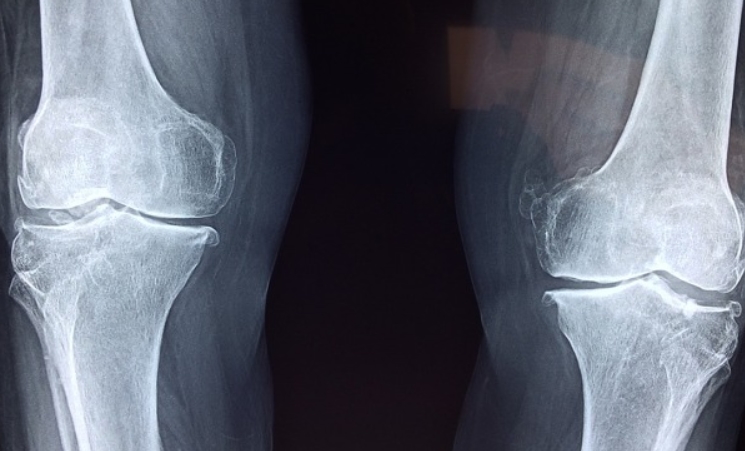

예전에 저희 엄마가 무릎이 시큰거리신다고 하셨을 때, 처음 들었던 말이 바로 ‘글루코사민’이었어요. 알고 보니 이 성분은 우리 몸속에서 자연스럽게 만들어지는 아미노당(당과 아미노산이 결합한 성분)으로, 관절 사이를 부드럽게 이어주는 윤활액과 연골의 주성분 중 하나라고 하더라고요.

하지만 나이가 들수록 글루코사민의 생성이 줄어들고, 그 결과 관절이 마모되거나 뻣뻣해지기 쉬워집니다. 엄마도 처음엔 계단 오를 때 무릎이 찌릿찌릿하다고 하시더니, 시간이 지나면서 앉았다 일어나는 것도 버겁다고 하시더라고요. 그때부터 글루코사민을 챙기기 시작하셨고, 몇 개월 후에는 확실히 덜 아프다고 하셨어요. 글루코사민은 몸속 연골의 건강을 돕고, 관절의 유연성을 유지하는 데 꼭 필요한 성분이라는 걸 그때 실감했습니다.

이 성분은 관절 안쪽에서 연골이 닳는 걸 방지하고, 손상된 연골이 회복되도록 돕는다고 해요. 게다가 관절 내 염증 반응을 줄이고, 움직일 때 발생하는 뻑뻑한 마찰음을 줄여줘서, 일상에서 느끼는 통증이 점점 줄어드는 걸 체감하는 분들도 많습니다. 글루코사민의 효능 무릎, 손가락, 고관절 등 반복적으로 사용하는 부위에서 효과가 뚜렷하게 느껴진다는 후기들이 많습니다.

첫째, 관절 통증을 줄여주는 작용이 있습니다. 평소 걸을 때 무릎에서 소리가 나거나, 뻐근한 통증이 있었던 분들이 글루코사민 복용 후 부드러워졌다는 경험담을 많이 공유하세요.

둘째, 연골 마모를 늦추고, 필요에 따라 어느 정도 재생을 유도하기도 합니다. 물론 심하게 손상된 연골을 완벽히 되돌릴 순 없지만, 일상생활을 하는 데 있어 증상이 완화되는 건 큰 도움이 되지요.